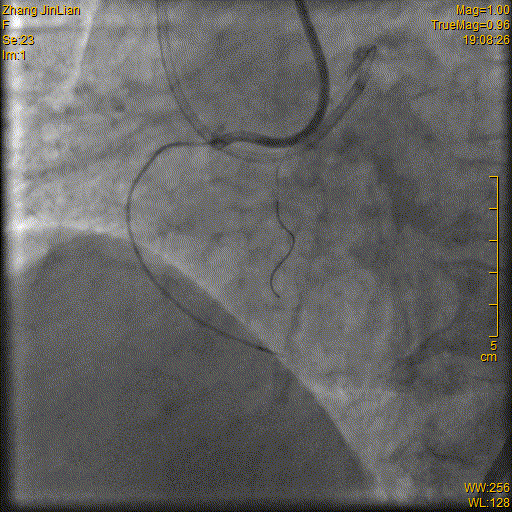

4. RCA PCI:Runthrough导丝保留在LAD行逆向PCI准备,Runthrough导丝引导Corsair150MC进入RCAm, 更换Fielder XTR导丝远端打弯(图11),导丝升级为PILTOT150耐心操作进入远端真腔(图12),Corsair150MC通过闭塞段(图13),更换工作导丝,2.0×15mm球囊扩张RCAm-d扩张后仍有明显狭窄(图14),2.5×29mm、2.75×23mmFirebird2DES串联植入RACp-d(图15-16),后三叉以远不显影,预计严重狭窄(图17),2.0×15mm球囊扩张后狭窄改善(图18),在Guidezilla延长导管支撑下20×23mm药物球囊扩张扩张后三叉60sec,最终效果满意(图19-20)。

图13

图14